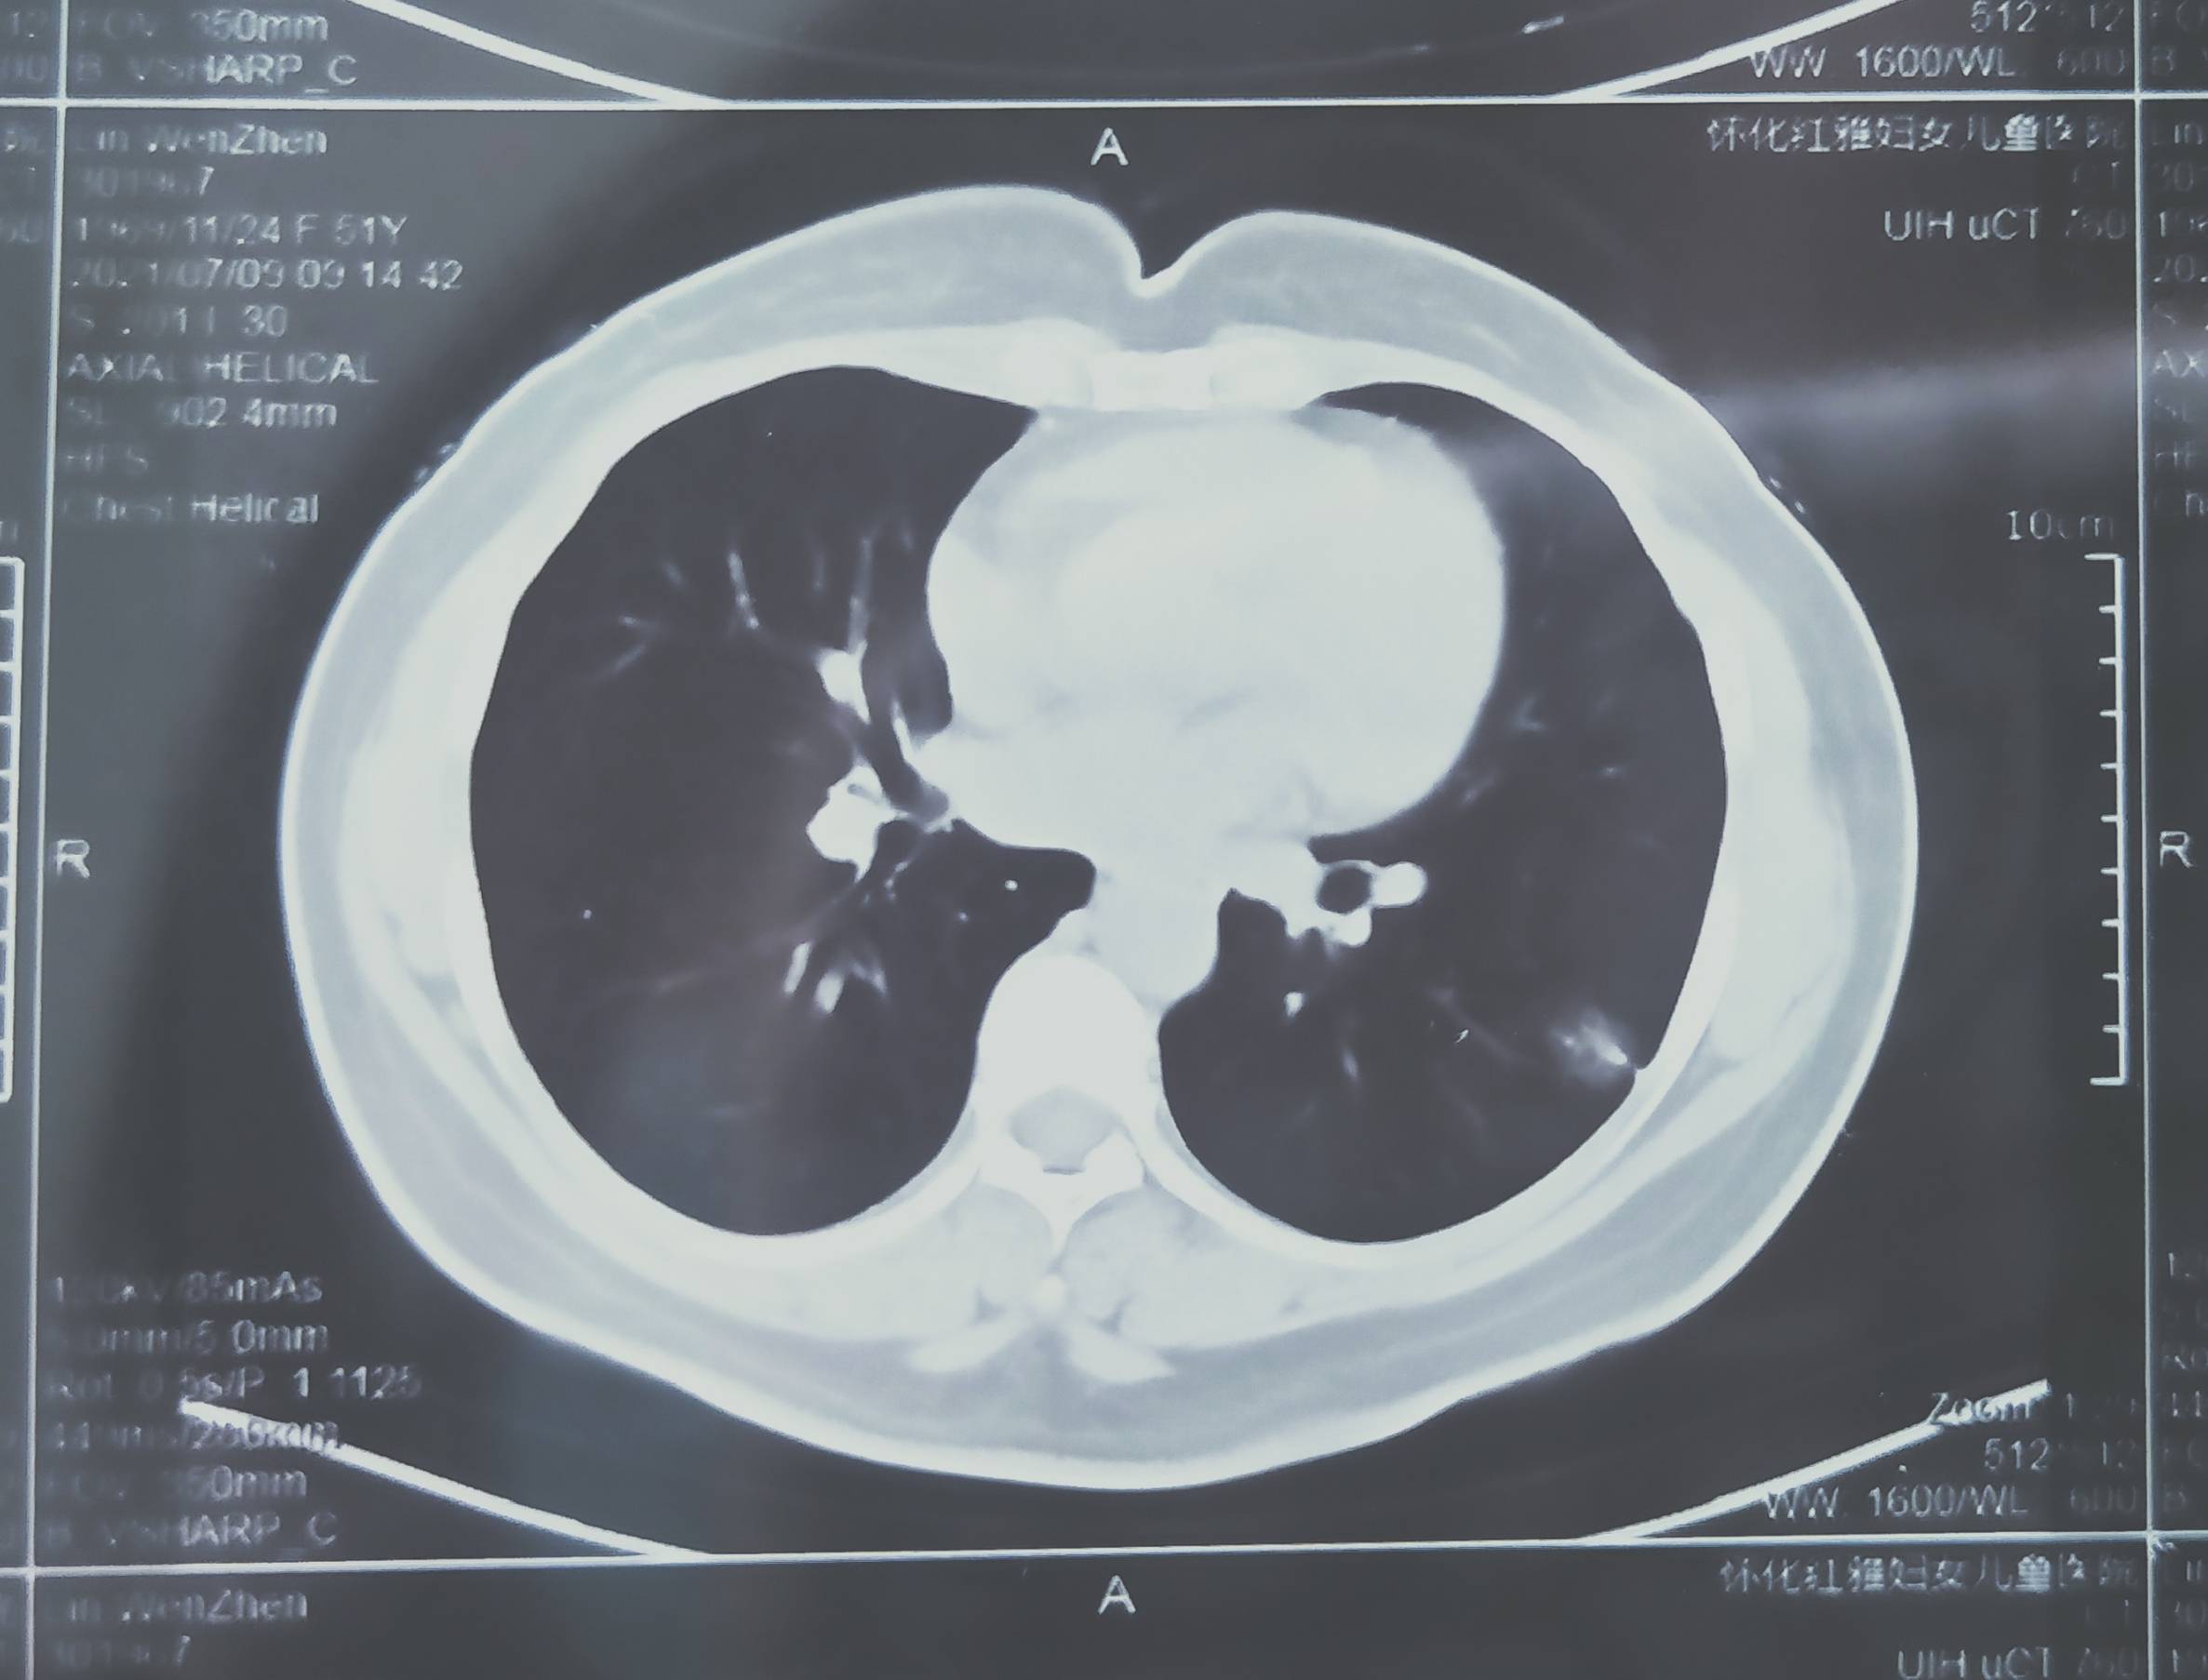

肺腺癌,胸膜粘连,没做弹力纤维染色

母亲术后病理是肺腺癌,CT上也写了与邻近胸膜粘结,但是手术医生没有把胸膜取下来做病理。不知道有没有胸膜侵犯。怎么办啊?其它没有转移,就怕有胸膜侵犯。术后没有治疗。